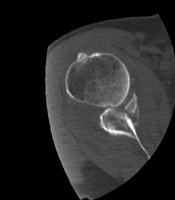

- Click on the image for a larger versionCAxial CT. This image shows a Bankart fracture.